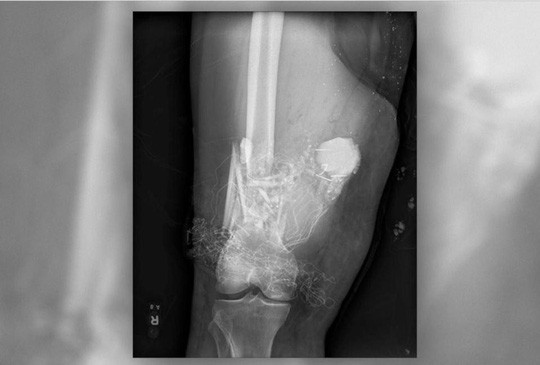

Phim X-quang cho thấy cây pháo bông găm khá sâu vào đùi bệnh nhân - Ảnh do bệnh viện cung cấp.

Một bệnh nhân 44 tuổi đã được đưa tới bệnh viện quân y San Antonio ở bang Texas, Mỹ, sau khi bị pháo giống như đạn cối găm vào đùi. Kết quả chụp X-quang cho thấy quả pháo có thể nổ bất cử lúc nào.

Lo ngại thiết bị có thể bùng nổ bất cứ lúc nào và gây sát thương cho kíp mổ lẫn bệnh nhân, các bác sĩ đã liên lạc với đội kỹ thuật viên Xử lý Chất nổ (EOD), tức một đội gỡ bom – phòng cháy chữa cháy chuyên nghiệp của quân đội.

Theo chỉ dẫn của lực lượng phá bom mìn, các bác sĩ đã sử dụng nước để làm mát vết thương của bệnh nhân và tránh quả pháo phát nổ. Họ cũng được yêu cầu tránh sử dụng các thủ thuật làm nóng da bệnh nhân trong khi phẫu thuật. Bệnh nhân đã được phẫu thuật loại bỏ cây pháo bông, cố định xương gãy bằng một thanh kim loại, điều trị chấn thương phần mềm và ghép da.